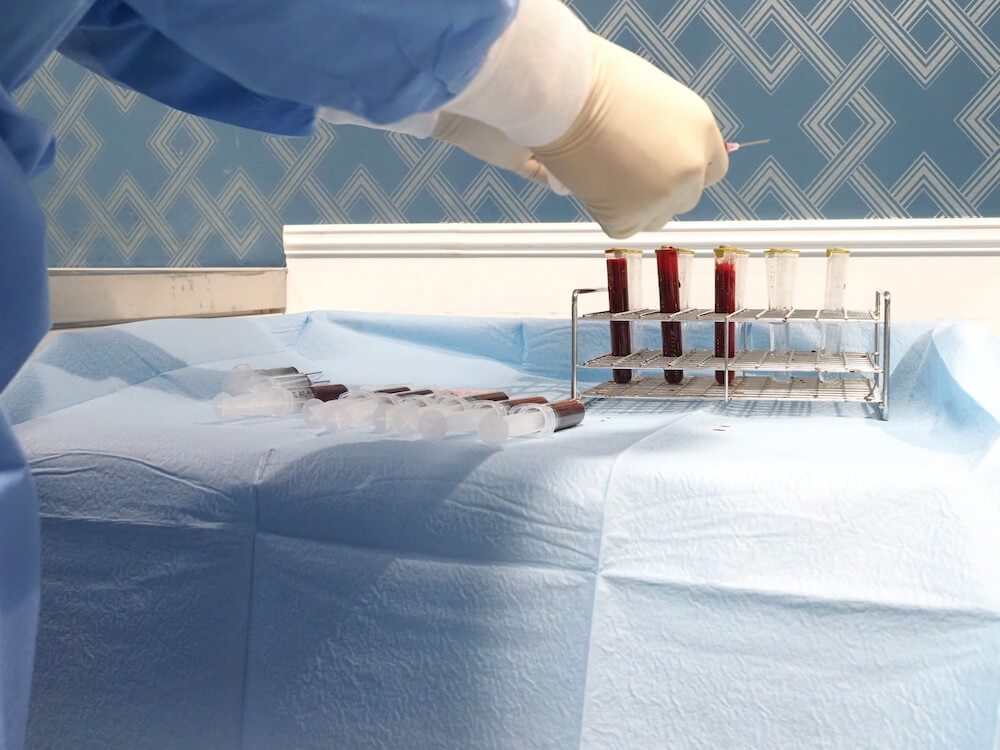

骨髄間葉系幹細胞は、骨髄の中にある幹細胞のことで、骨髄穿刺(骨に針を刺す)ことで採取することができます。骨髄穿刺(こつずいせんし)は、従来から広く行われている手技であるため、安全な方法が確立されています。

骨髄由来の幹細胞は患者様ご自身より採取して治療を行います。具体的な治療プロセスは、「採血(感染症検査)→骨髄液の採取→幹細胞の培養→幹細胞の投与」となります。